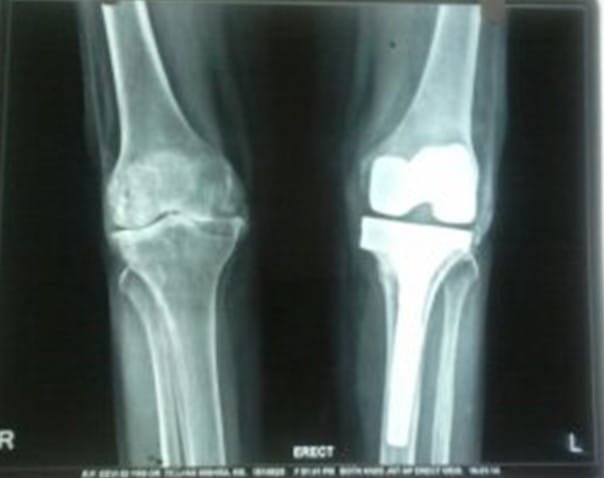

Although there has been an attempt to perform knee replacement in the 19th and early 20th century, Total Knee replacement surgery has come a long way since 1970s with continuous improvement in the design of implants and fixation techniques. Success from Charlney’s hip replacement surgery got surgeons and engineers interested again leading to modern-day implants. It has been successfully being performed worldwide from 1980 onwards. Diseased part of femur and tibia are removed using special instruments and metal implants mimicking design of femur and tibia are inserted using antibiotic-laden polymethyl methacrylate (bone cement). A polyethylene inset is fixed onto the tibial implant thus allowing movement at the knee joint. The undersurface of patella may be replaced with a patellar button in some cases. Due to improved technique and implant design, this surgery has gained immense popularity and has given a new lease of life for the patients suffering with arthritis of the knee joint. Patients can walk comfortably with the help of support following surgery and aren’t dependent on others for day-to-day life activities. Quality of postoperative care in recent times has further boosted the confidence among the patients undergoing this surgery. Patients are taught to strengthen the thigh muscle post-operatively and encouraged to become mobile. Gradually, they learn to climb stairs and later they walk around independently without any aided support. It is recommended that patients should not sit on the floor or squat. This helps maintain the longevity of the implants. As per the American Association of Orthopaedics, success rate of total knee replacement after 15 years is almost 90% and at the end of 25 years is almost 82%.

In total knee replacement surgery, we remove the damaged area over the femur, tibia and patella in the knee joint. It is replaced it with metal implants which are in the shape of these bones. These metal implants are fixed over your bone with the help of bone cement. Implants come in various sizes and you will get the best fit suited for you.